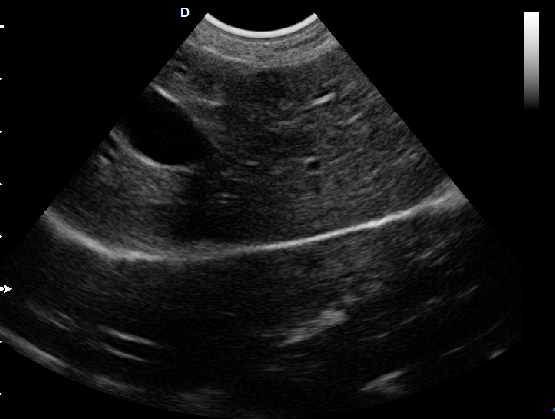

P5-VET便攜獸用彩超機適用對象:

牛羊馬豬犬貓及多種家禽、實驗動物、野生動物、及部分水生動物。

P5-VET便攜式獸用彩超機

P5-VET獸用彩超機應用范圍:

適用于各種動物的臨床腹部、胸腔,心臟、肌腱、小器官、眼球、生殖系統等的檢查